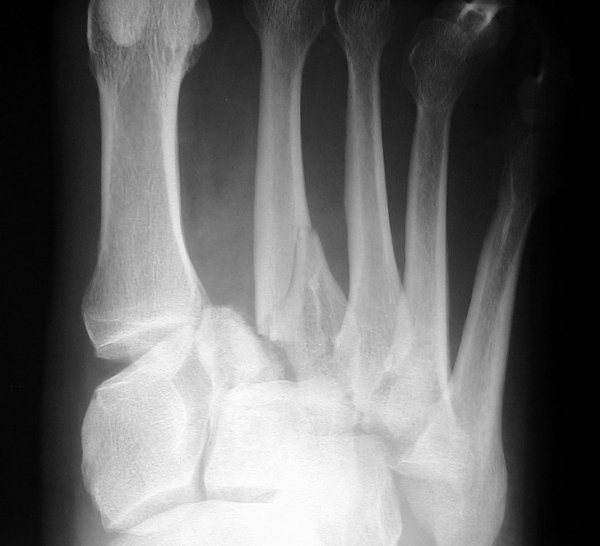

Return to Lisfranc Fracture-Dislocation